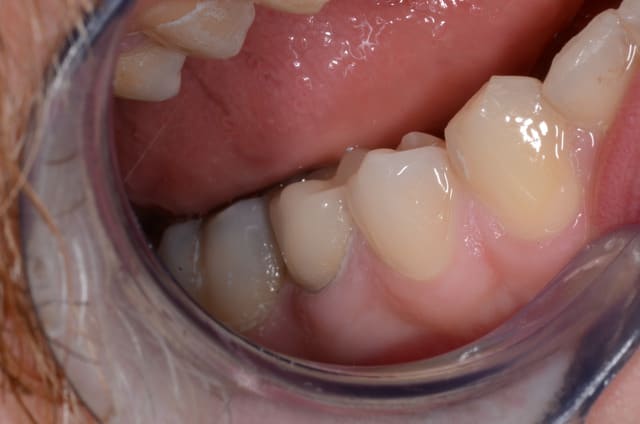

j'attends son installation...tiens en attendant, ce matin en une séance fauteuil 46 et 47.

Photo 080 bvrcp0 - Eugenol

Smile beach jgh0a1 - Eugenol

La 6 jolie, la 7 moins...mais qui va s'en plaindre ?

C'est du e.max ?

Combien de temps et de roro la séance ?

Vita markII

1h45 car le logiciel 3.85 a de fâcheuses tendances au bugs, et usinage plus long pour endocouronnes molaires , 550€/couronne.